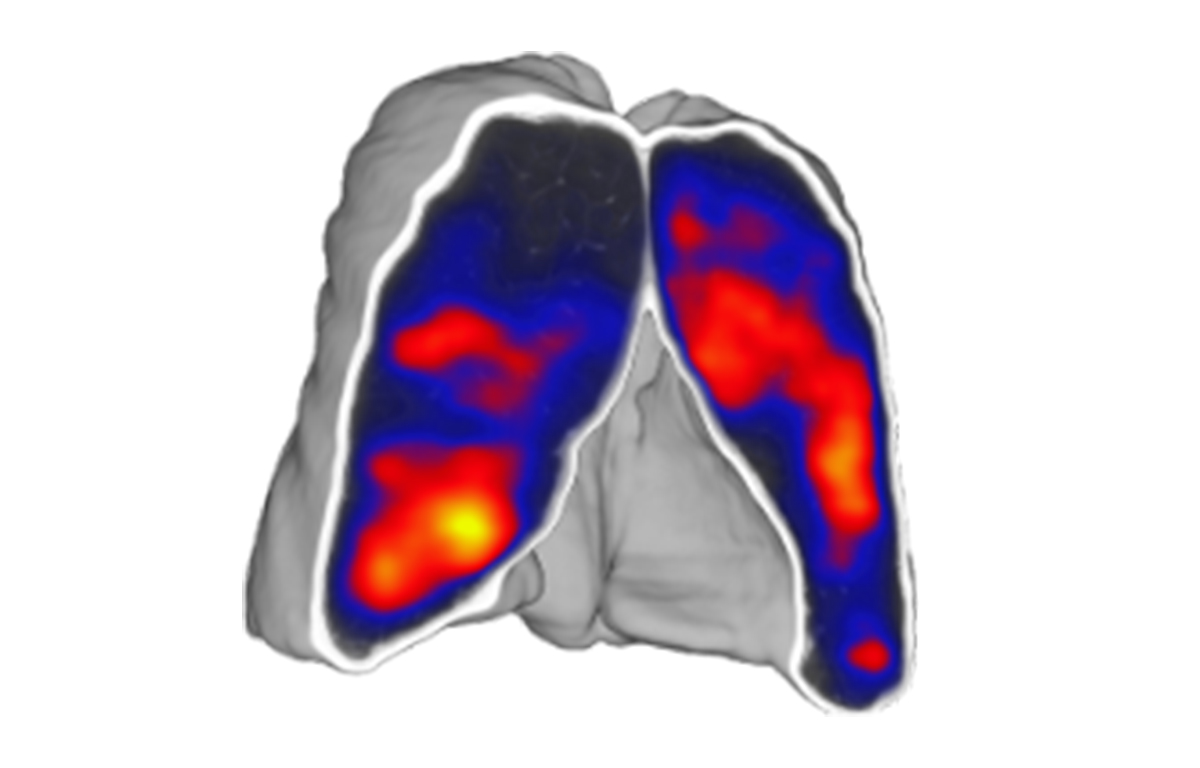

Built on advanced capabilities in lung segmentation and quantification, our AI technology interprets thoracic CT data with anatomical precision - capturing airway trees, parenchymal patterns, and vascular structures, even in severely diseased lungs.

- Quantitative analysis of complex lung patterns and diseased regions

Emphysema / Hyperinflation

- BLVR Implants

- Parenchymal Ablation